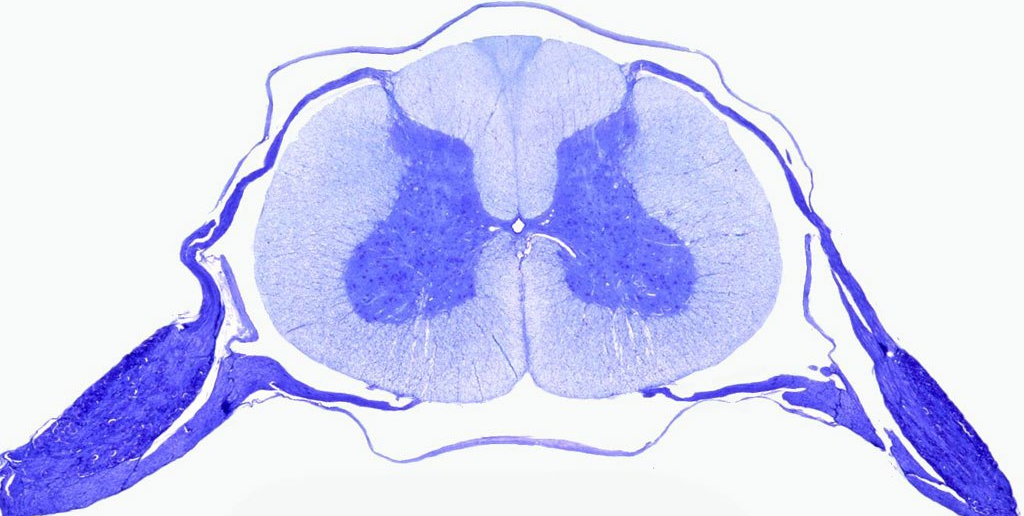

Know your spinal cord – Motor neuron disease

Kultschitzky staining was used here and shows marked symmetrical demyelination (whitening regions) in the anteriolateral roots (especially pyramidal tract) of the spinal cord

It’s day twenty-six already! For those of you who are just finding us, you can find all of the posts in our super cool neuroanatomy category. We’ve already covered a lot of spinal disorders, but one of the larger diseases that we have yet to cover is motor neuron disease. Technically a family of diseases, we will look at the commonalities and causes, so with that introduction, let’s get going.